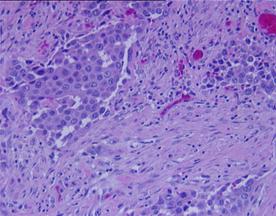

a) b)

Fig.6 Aspecte microscopice. a) Carcinom urotelial cu grad inalt de malignitate (Hex10) b) Invazie tumorala in intesitiile muscularei propii. (Hex5). [51].